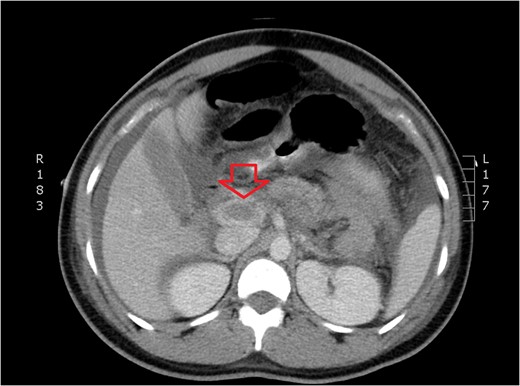

CT of dilated portal vein and extension of thrombosis (axial view).

The patient presented to the emergency room the evening of POD 3 with emesis and obstipation. Her vital signs and laboratory values were normal. An x-ray showed small bowel dilation and she was readmitted for postoperative ileus. A nasogastric tube was placed and the patient was started on IV fluids. Upon worsening pain and tachycardia on POD 4, a computed tomography (CT) scan with triple contrast was obtained. The CT scan showed evidence of PVT (Figs 1–3). The patient was transferred to the ICU and started on a therapeutic heparin. She improved clinically and was discharged home with rivaroxaban on POD 8. A hematologic evaluation was negative for disorders of factor V Leiden, antithrombin III, homocysteine and cardiolipin.